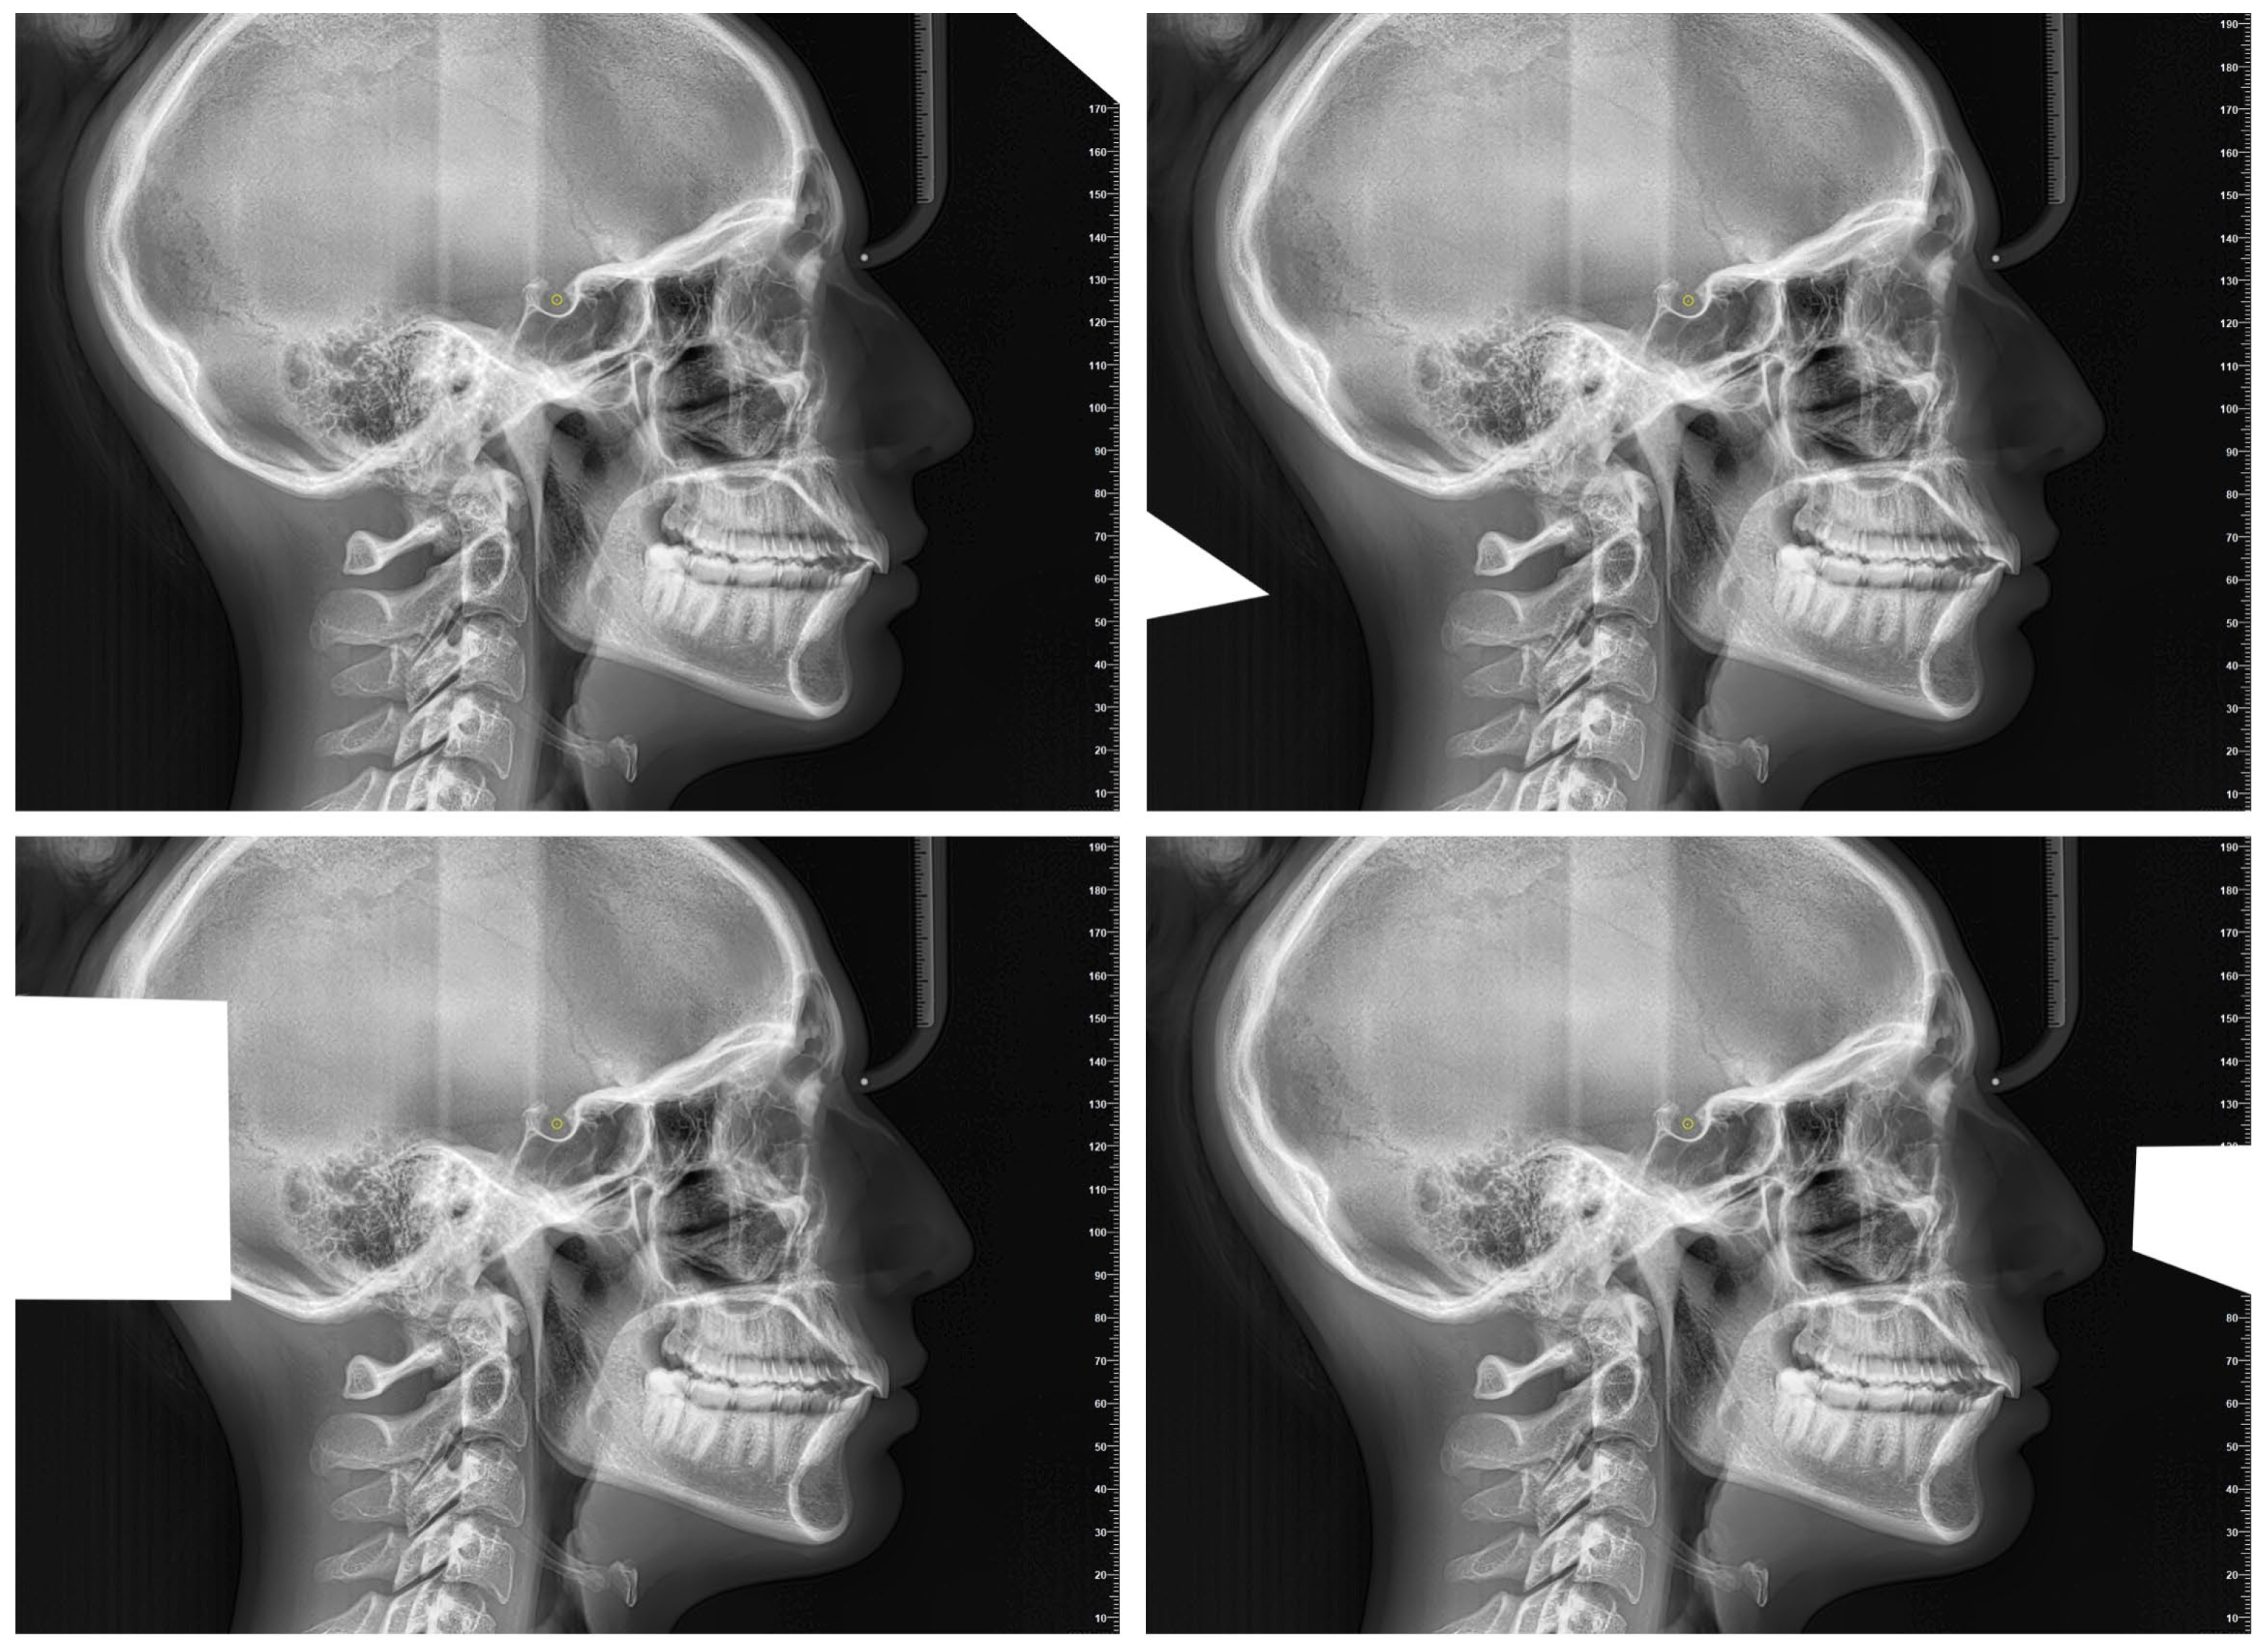

- Artificial Intelligence Cephalometric Tracing—With Image Modification (AIcut):The same AI model was used to detect landmarks, but the image was intentionally resized or cropped in each of the 10 repetitions. This aimed to test the AI’s robustness and precision under altered input conditions (Figure 2). The image cropping was intended to alter the grayscale values at the image margins, which represent one of the parameters used by the AI to orient itself within the radiograph. Importantly, the introduction of these crops did not in any way affect the anatomical structures relevant for landmark localization.